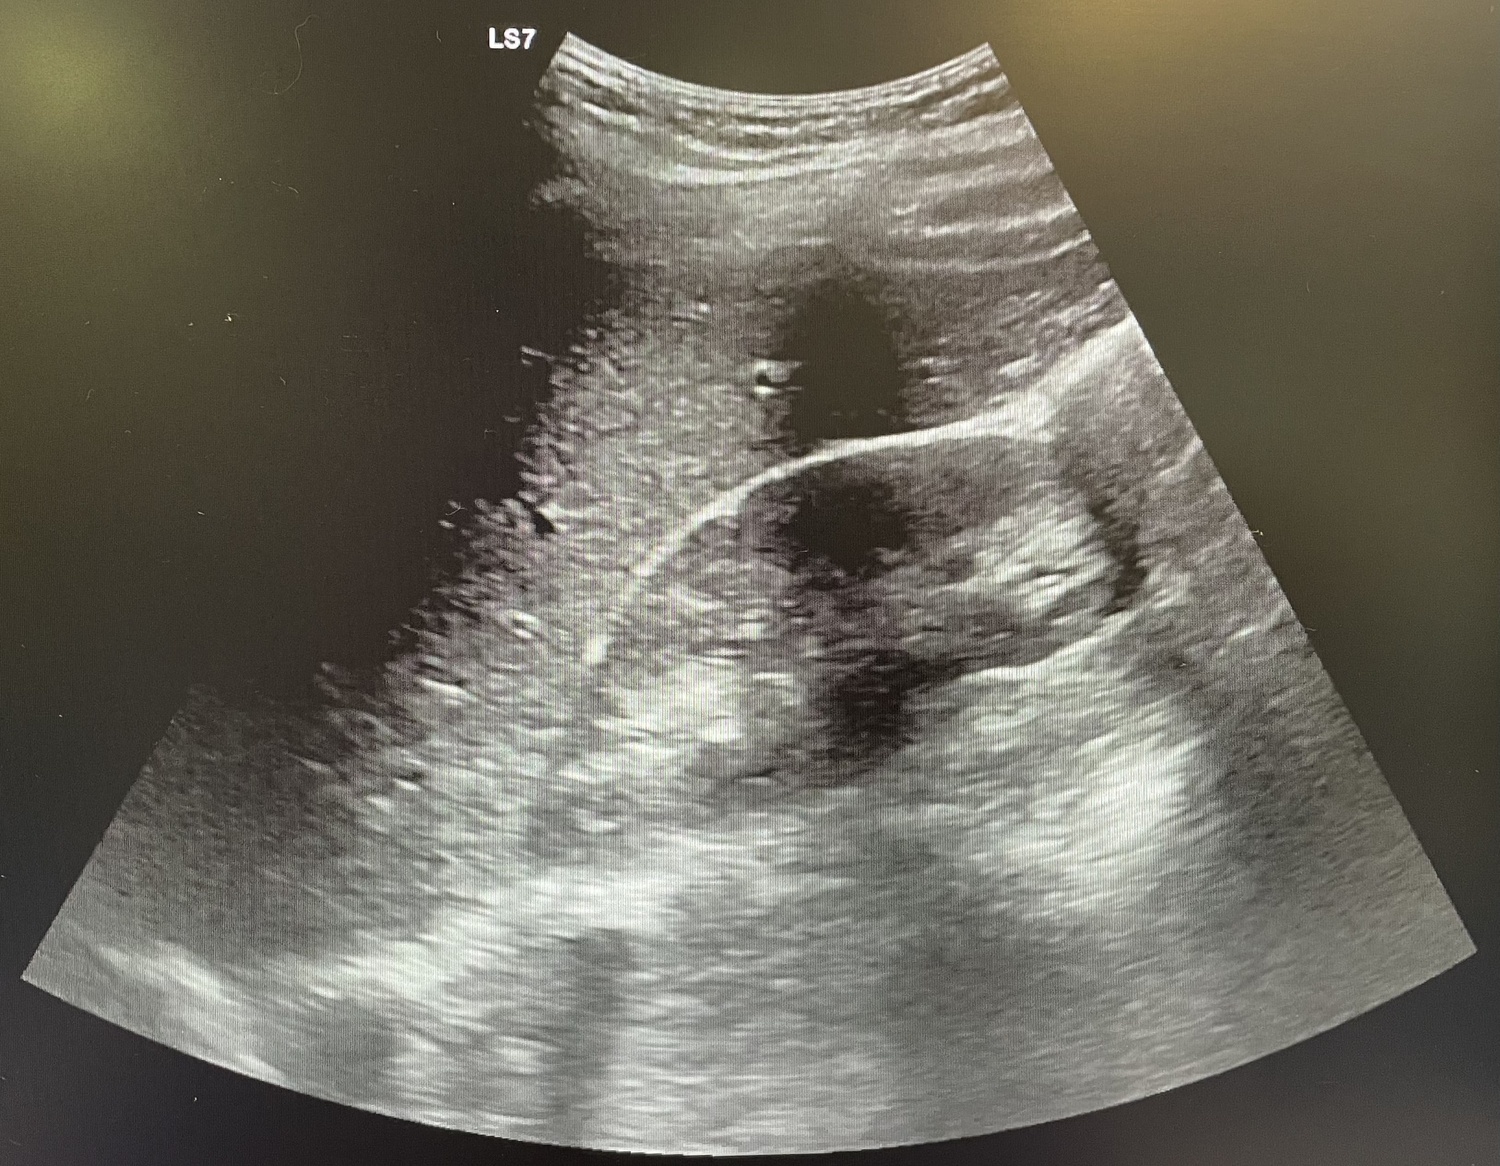

Se realiza analítica con aumento de reactantes de fase aguda (leucocitos 18.00 y PCR 108) y se indica ecografía abdominal que resulta no concluyente, por lo que se procede a alta.

Al día siguiente vuelve con la misma sintomatología, el dolor no cede con analgesia habitual. En la exploración Blumberg claramente positivo, se solicita analítica (leucocitos 13.000 y PCR 127) y se repite ecografía de abdomen que se sigue informando como no concluyente para apendicitis aguda.